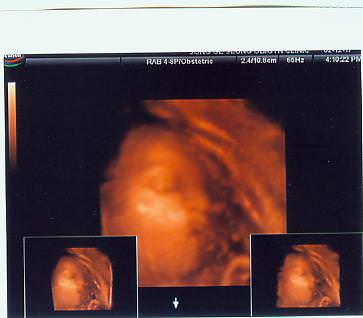

우리 딸이 오늘도 속을 썪여서 2시간이나 병원에 죽치고 있어야 했어요.   소문이 자자하답니다.   비싼 몸이라고...

볼이 눌려서 외계인같아요.

그래도 눈,코,입 다있어요^^;;